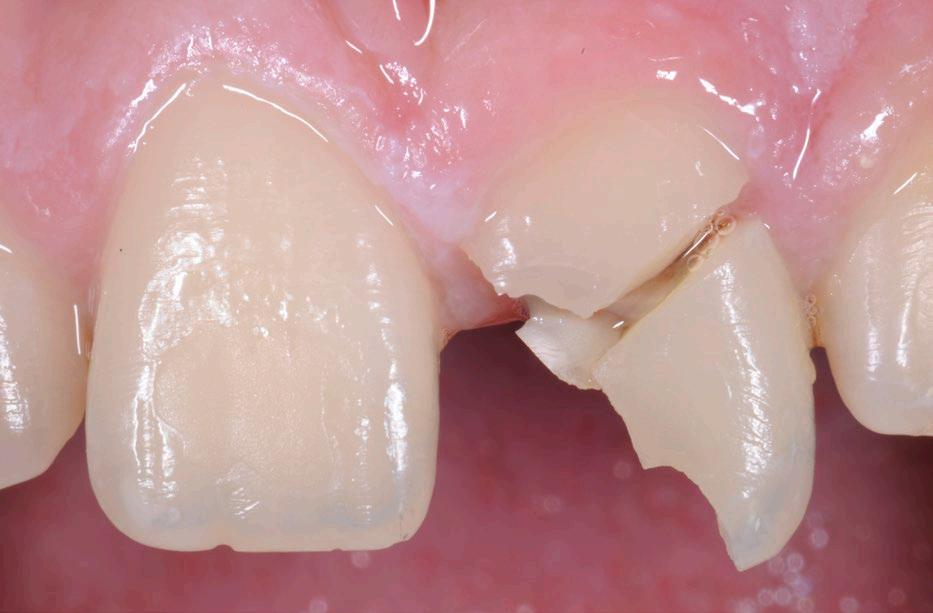

Po zvládnutí akutních obtíží se stanoví léčebný plán, který se řídí jasně definovaným postupem. Nejprve je nutné odstranit příčinné faktory a vyřešit méně akutní situace, jako je rekonstrukce zlomeného zubu,

který způsobuje estetické problémy nebo má ostré hrany či hroty, a to i když nepůsobí bolest. Do této první fáze spadá také extrakce zbytků kořenů či zubů, které nelze zachránit.